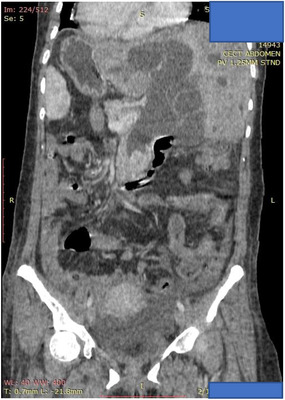

A 42‐year‐old female with no prior medical illness presented with fever, epigastric pain, and vomiting of 3 days’ duration. On assessment in the Emergency Department, she appeared septic with a blood pressure of 70 of 46 mm Hg and a pulse of 98/min. Temperature was 37.5°C. Further examination revealed that she was icteric. She had crackles on both lung bases with the apex beat appreciated at the right 5th intercostal space. Blood parameters were notable for deranged Liver Function Test with total bilirubin, 5.4 mg/dL; aspartate aminotransferase (AST), 481 U/L; and alanine aminotransferase (ALT), 333 U/L. The Blood Film for Malaria Parasite which was positive for Plasmodium Falciparum added to the complexity of the case. Radiographic imaging of the chest was consistent with situs inversus. She was initiated on antibiotics, antimalarials, and vasopressors. CT imaging revealed choledocholithiasis with upstream dilatation of the biliary tree (Figure 1). There were no associated anatomical abnormalities of the CBD. The size of the CBD stone (2.2 × 1.8 cm) depicted on the CT had raised concerns on the amenability of an endoscopic intervention in achieving stone clearance. However, during the multidisciplinary meeting, a decision was reached to proceed with ERCP and biliary decompression as a temporizing measure in view of the anticipated delay in surgery due to ongoing COVID‐19 pandemic. Patient was placed in supine position with the endoscopist on the left side. The supine position was preferred by the anaesthetist for better control of the airway in the event of a desaturation episode. Following administration of sedation with propofol (100 mg), ERCP was performed with a side‐viewing endoscope (TJF‐Q180V J; Olympus, Tokyo, Japan). The endoscope was advanced into the duodenum and was rotated 180° clockwise with some degree of torsion. The papillary orifice was noted in the 2 o’clock direction, with the scope in long position. Owing to the location of the papilla, a rotatable sphincterotome (Leo Med triple lumen sphincterotome RST0725N, Leo Medical Co., Ltd, Changzhou City, Jiangsu Province, China) (Figure 2a) was employed to achieve deep biliary cannulation. Cholangiogram revealed a large mid CBD stone following which, a wire‐led sphincterotomy was performed (Figure 2b). Fluoroscopy image was mirrored to make cholangiogram interpretation more familiar. We then advanced a stone extraction catheter (Leo Med stone extraction catheter QS‐2A00, Leo Medical Co., Ltd, Changzhou City, Jiangsu Province, China) into the CBD and after inflating it we used the balloon as an anchor to perform the shortening manoeuvre of the duodenoscope (Figure 3a). This was essential as we had anticipated technical difficulty in extracting the stone owing to the axis between the 2 o’clock position of the ampulla and the duodenoscope. This manoeuvre was done by maintaining traction on the duodenoscope while performing a 180˚ clockwise torque. With this technique, we attained a short position of the endoscope (Figure 3b) and restored the papilla to the conventional 11 o’clock position (Figure 4). Nevertheless, attempts for CBD stone removal using an extractor balloon catheter failed in view of the size of the stone as well as the angulation of the duodenoscope. We proceeded with stenting using a straight plastic stent to decompress the biliary system. The procedure took approximately 35 min, and there were no episodes of desaturation throughout the procedure. Our patient had a favorable recovery following the procedure, with improvement of both clinical and biochemical parameters. She underwent Common Bile Duct Exploration (CBDE) and cholecystectomy 2 weeks following the ERCP procedure and was discharged well.